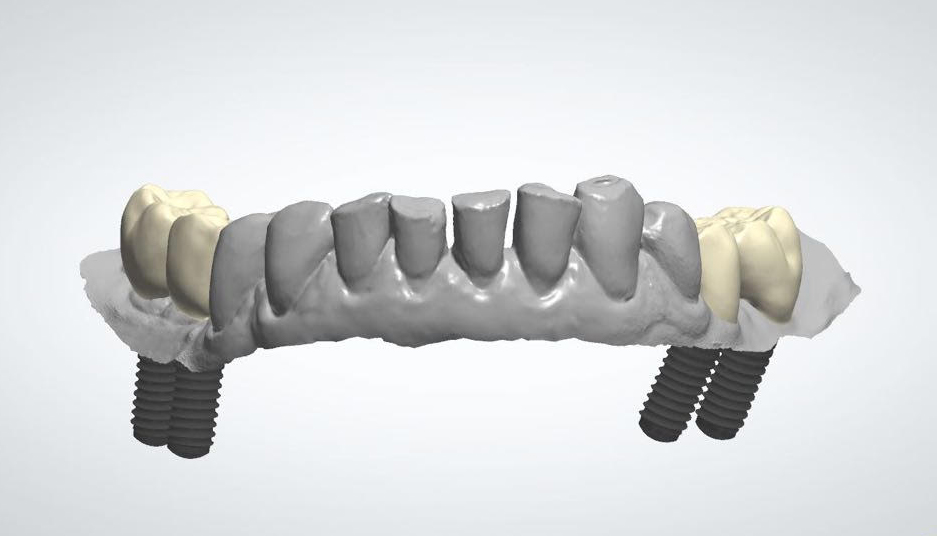

Der Zahnersatz wird in Aachen lokalisiertem Labor fertiggestellt. Das Labor verfügt über umfangreiche Erfahrung bei der Ausführung von zahnärztlichen Arbeiten sowohl in Keramik als auch in Metall: Inlay, Onlay, Overlay, Veneers, Kronen, Teilkronen aus allen Vollkeramikmaterialien und Hybriden und Zirkonium. Es wird insbesondere Folgendes ausgeführt:

• Vollkeramikbrücken – Brücken und Unterbauten aus Zirkoniumdioxid

• Implantat-Prothetik, Individualverbinder, Kronen und anschraubare Brücken und Zementbrücken